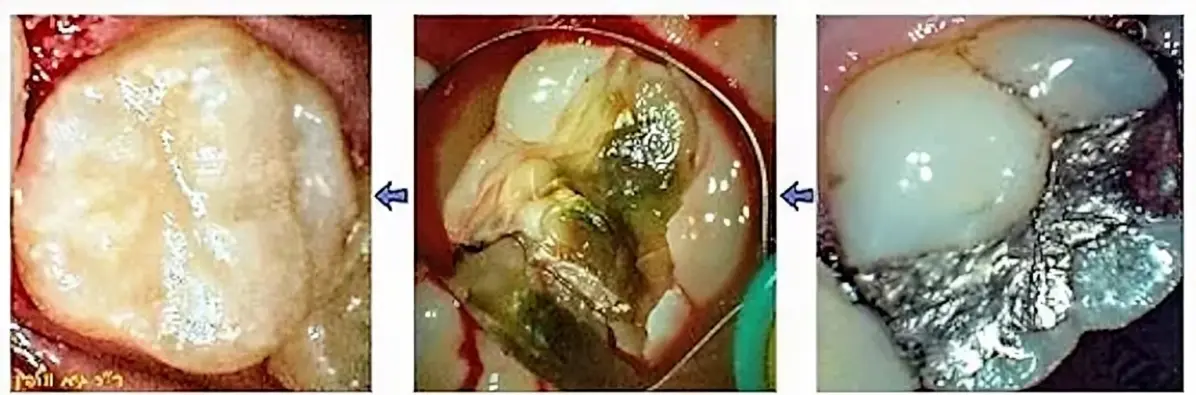

בתהליך כיפוי (=כיסוי) המוך, במידה והרופא איבחן שיש חור מאוד עמוק אך ככל הנראה עוד אין דלקת בעצב, רופא מנוסה ושמרני ינסה להציל את השן ולא מיידית להחליט על טיפול שורש או רק לעשות "סתימה": הרופא מורח באיזור העמוק ביותר חומרים מיוחדים שתפקידם לחסל חיידקים ולחזק את האיזור, ולבודד את איזור העצב שנחשף מחשיפה לאוויר ולחיידקים, למשל Theracal שמעודד בניית השן מחדש באיזור הפנימי ע"י שיחרור  calcium silicate וחומרים אנטיבקטריאליים אחרים. כמו כן נמרחים גם חומרים אחרים לחיטוי/ניקוי/הפחתת הרגישות שאופיינית לחורים עמוקים מאוד.

רק לאחר ביצוע כיפוי המוך ימשיך הרופא ויבצע את שיחזור השן והאנטומיה המקורית. כיפוי המוך הנ"ל משפר את הסיכוי של הצלחת הסתימה, לעומת סתימה "רגילה" עמוקה וללא כיפוי מוך. כמובן כל זאת בתנאי שעדיין לא מתפתח דלקת בעצב, נמק או זיהום.